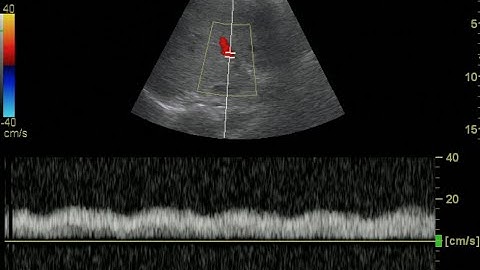

How to Get Great Pulsed Wave Doppler from the Main Portal Vein